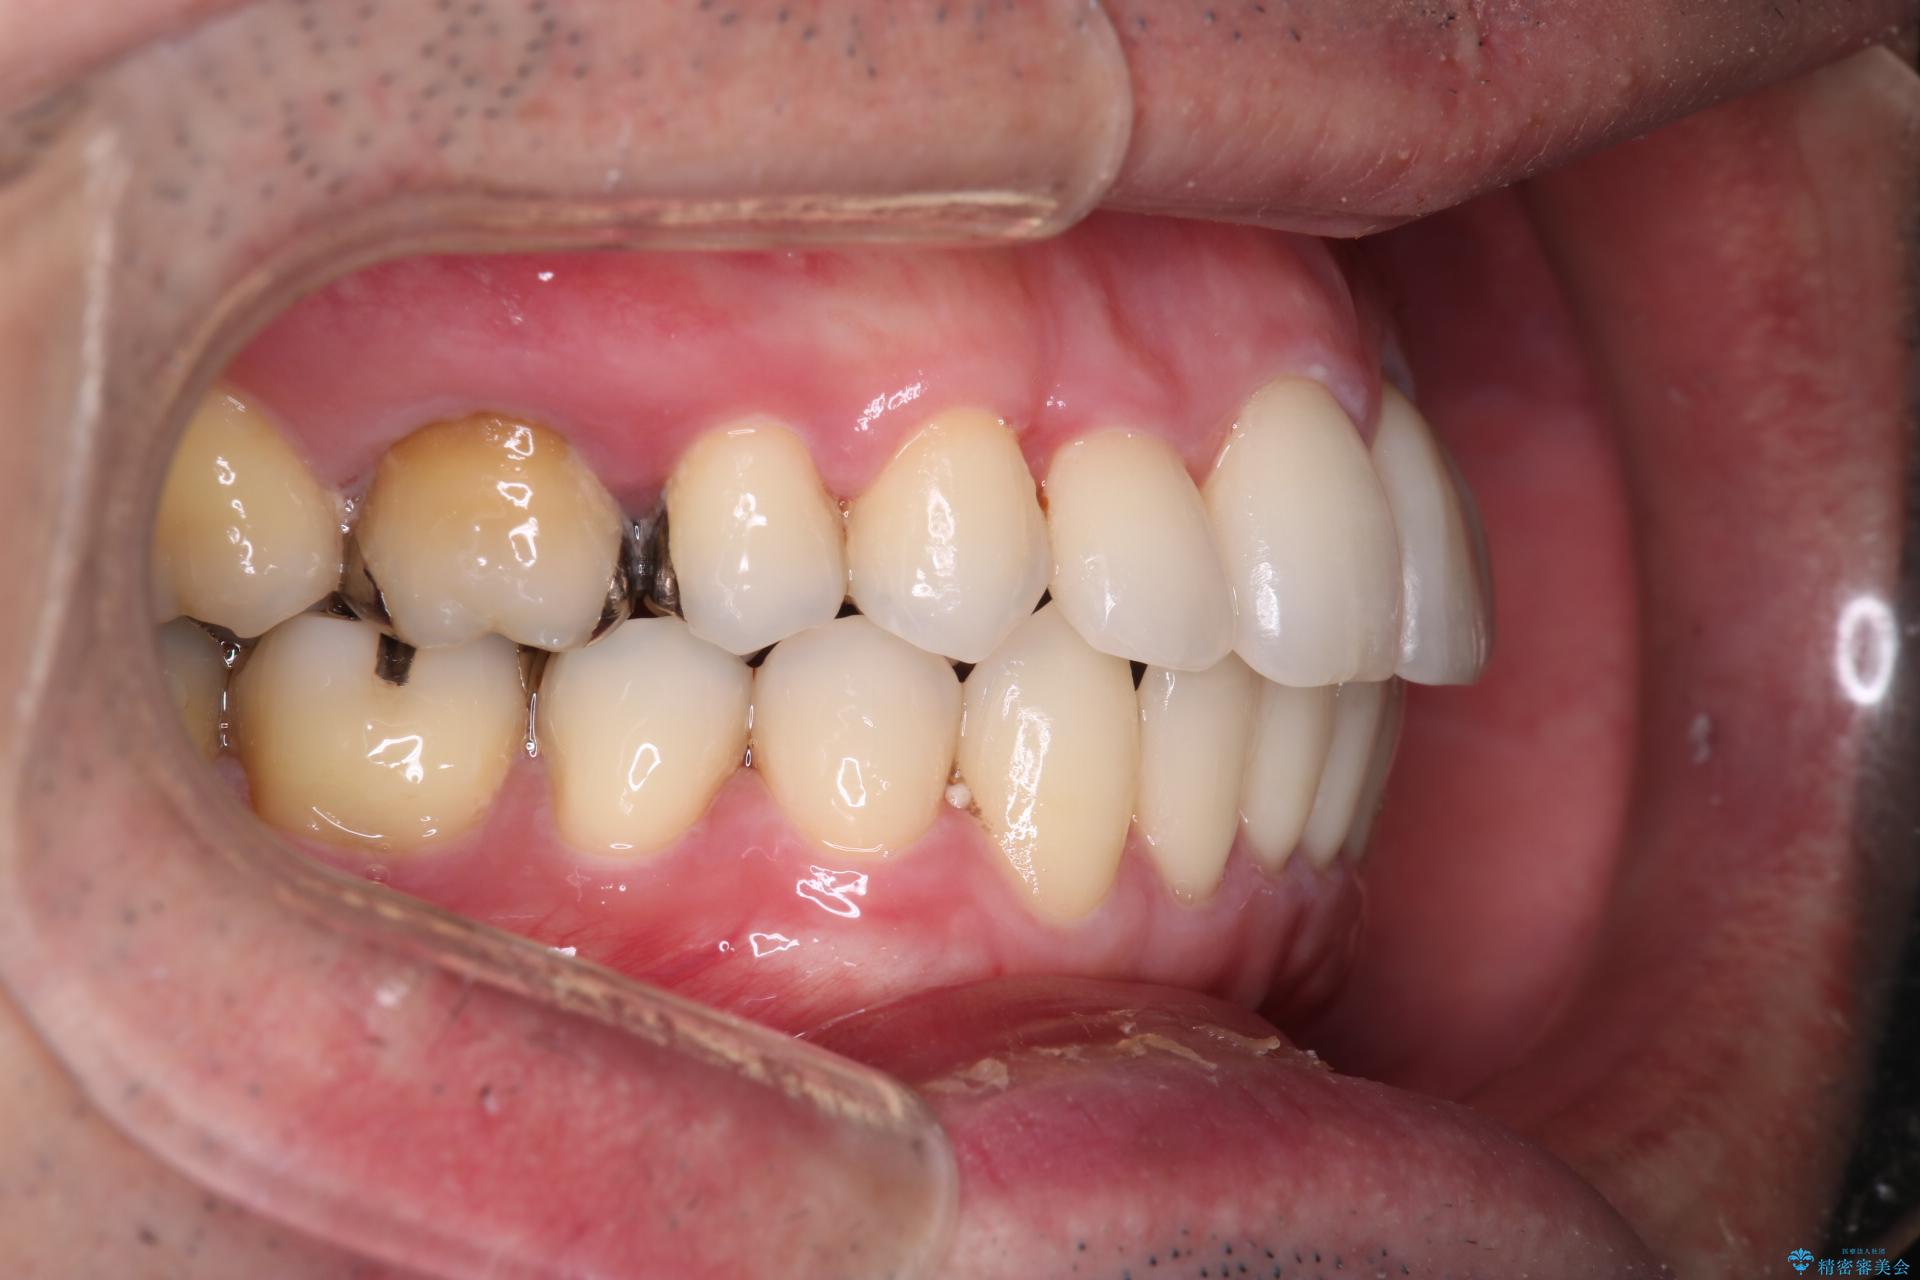

抜歯の本数を最小限に抑えたことで、治療計画も1年5ヶ月と短期間で終了することができ

主訴である前歯のがたつきも改善され綺麗な歯並びになりました。

矯正の装置を除去したタイミングで、ホワイトニングも行うことで歯の色味も白くなりました。